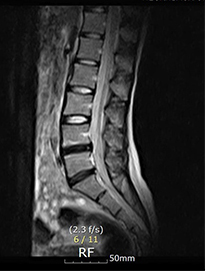

디스크내장증을 다른 말로 블랙디스크(black disc)라고 부르기도 하는데, MRI 검사 영상을 보면 디스크 부분이 검게 보이기 때문에 블랙디스크라고 부릅니다. 디스크 내의 수분이 빠지면서 탄성이 떨어지고 퇴행이 진행되어 검게 보이는 것인데요. 이처럼 아직 디스크가 탈출하지 않아 방사통이나 저림 증상이 없다고 하더라도 이미 퇴행이 진행된 상태라 이는 퇴행성 디스크의 일종이라 볼 수 있습니다.

디스크내장증은 디스크가 탈출된 것이 아닌

디스크만 퇴행된 것이므로, MRI영상으로 보면

신경이 지나가는길이 깨끗하다는 것

이 특징입니다.